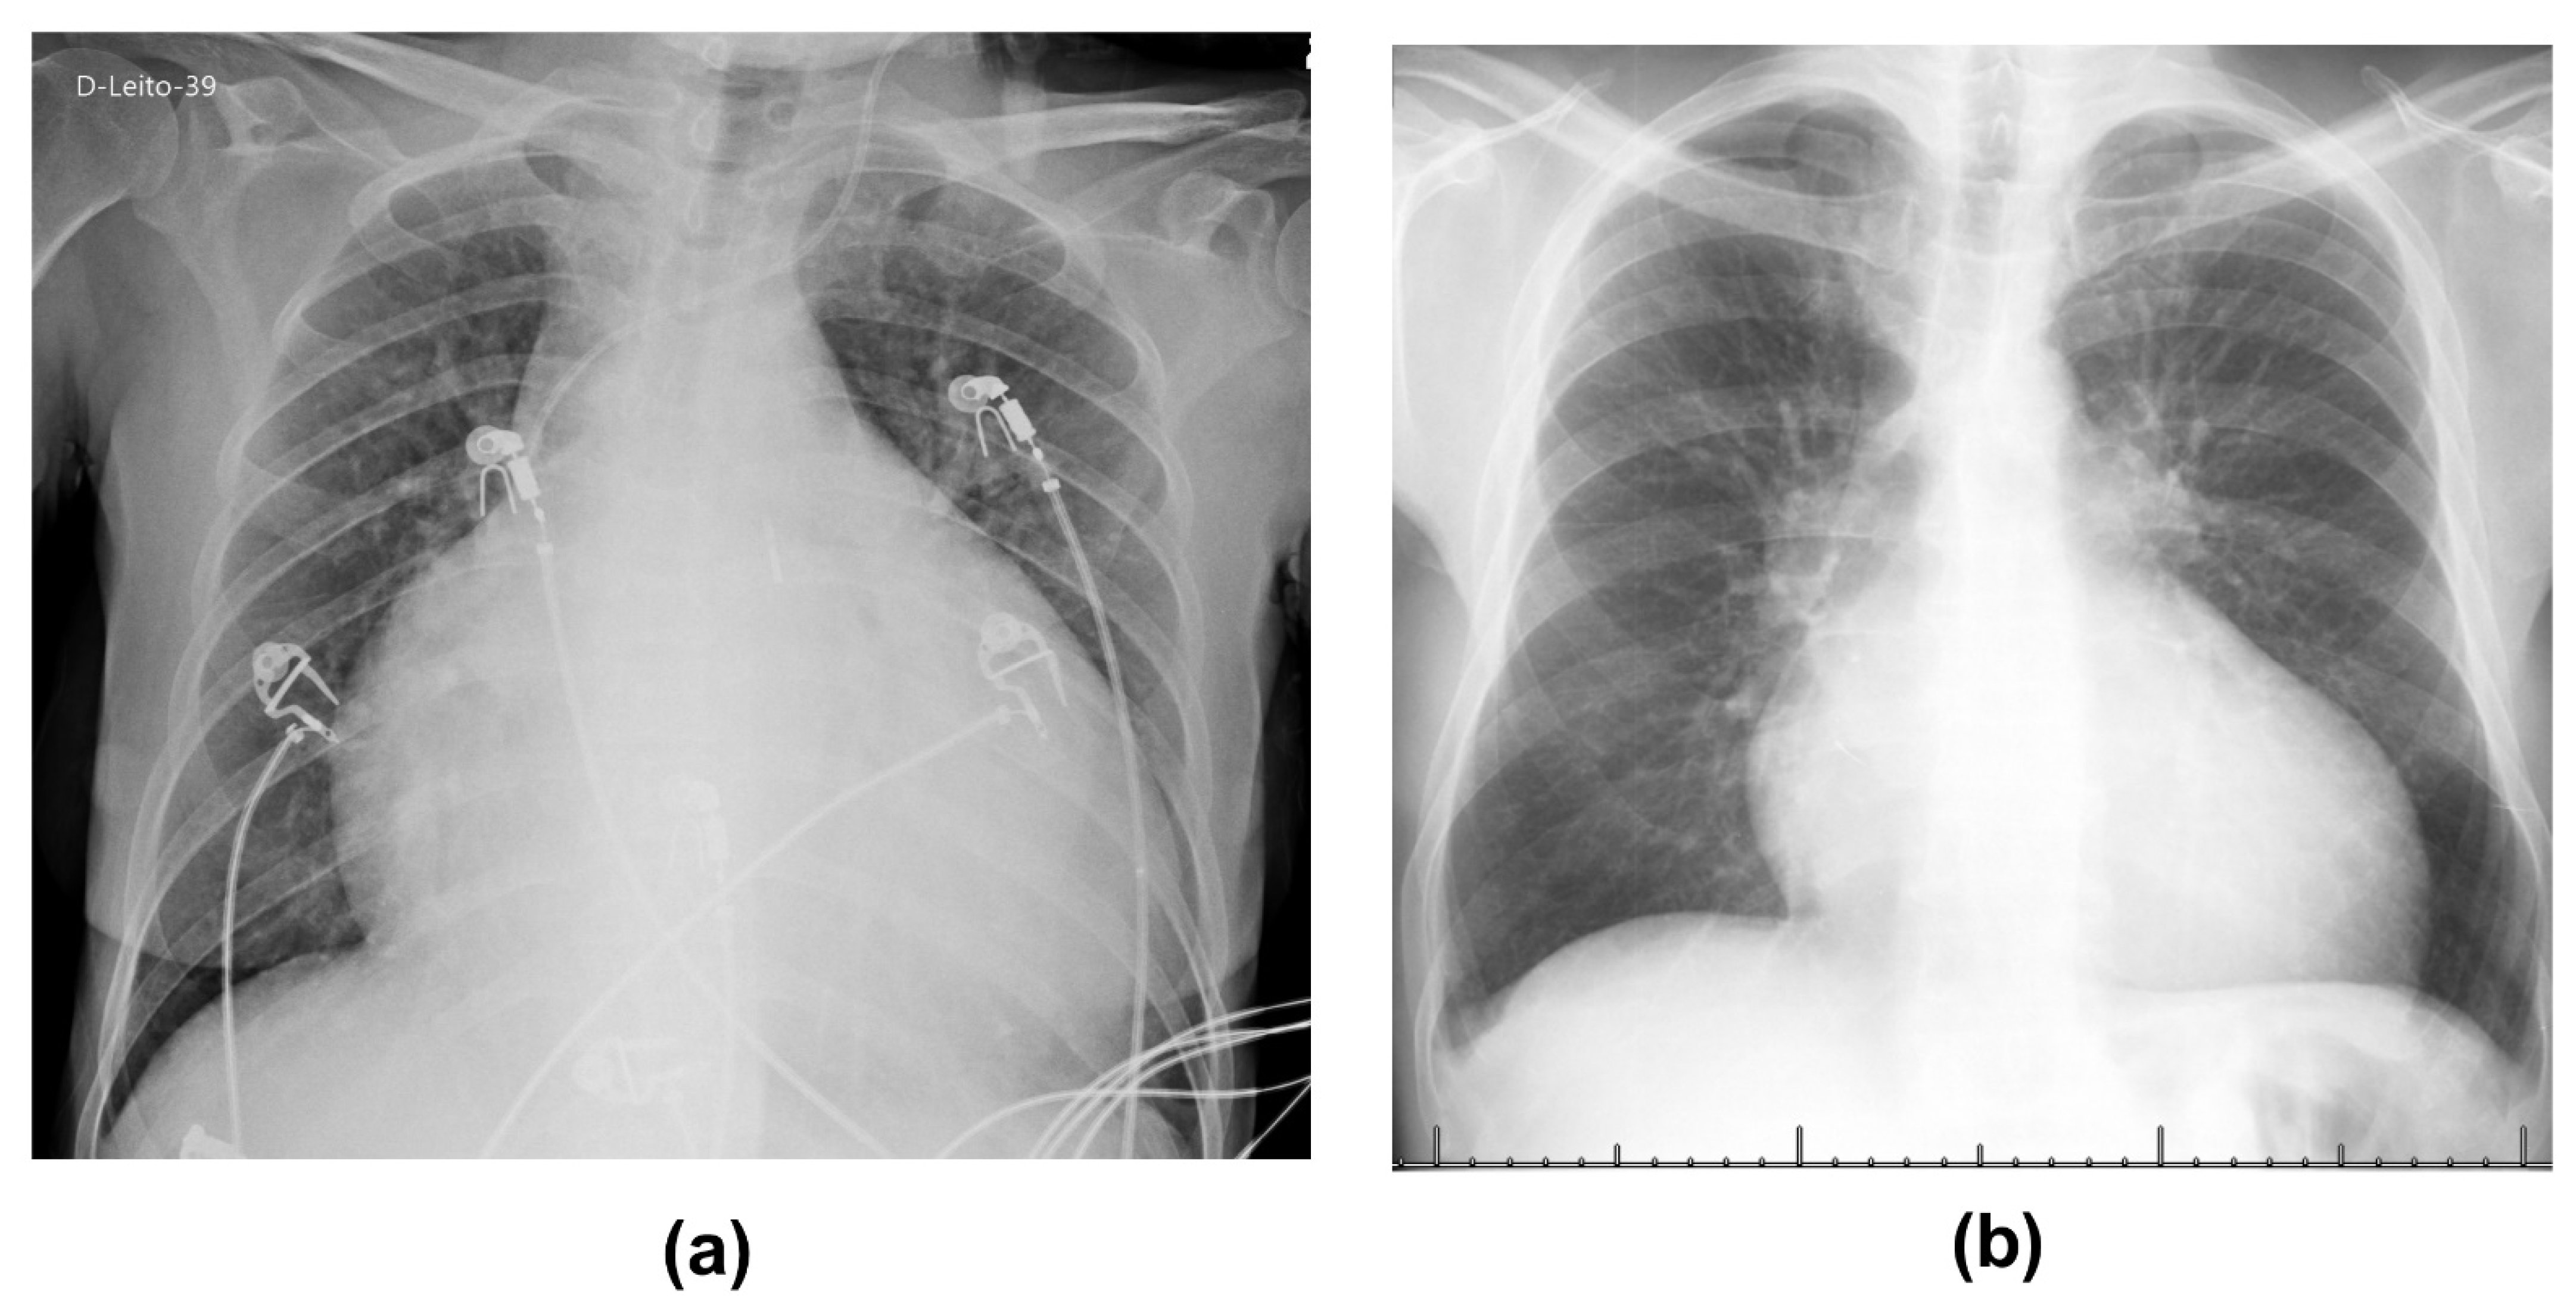

| Complications during ICU stay | ARDS due to COVID–19; heart transplant rejection, disseminated cytomegalovirus; aggravated chronic kidney disease and pressure ulcer | ARDS due to COVID–19, disseminated cytomegalovirus and pancytopenia due to hemophagocytosis |

| Previous comorbidities | Dilated cardiomyopathy of Chagas etiology, hypothyroidism by thyroidectomy by nodule 10 years ago | Cardiomyopathy of Chagas etiology, disseminated cytomegalovirus, deep vein thrombosis, systemic arterial hypertension, diabetes, dyslipidemia, and chronic renal failure |